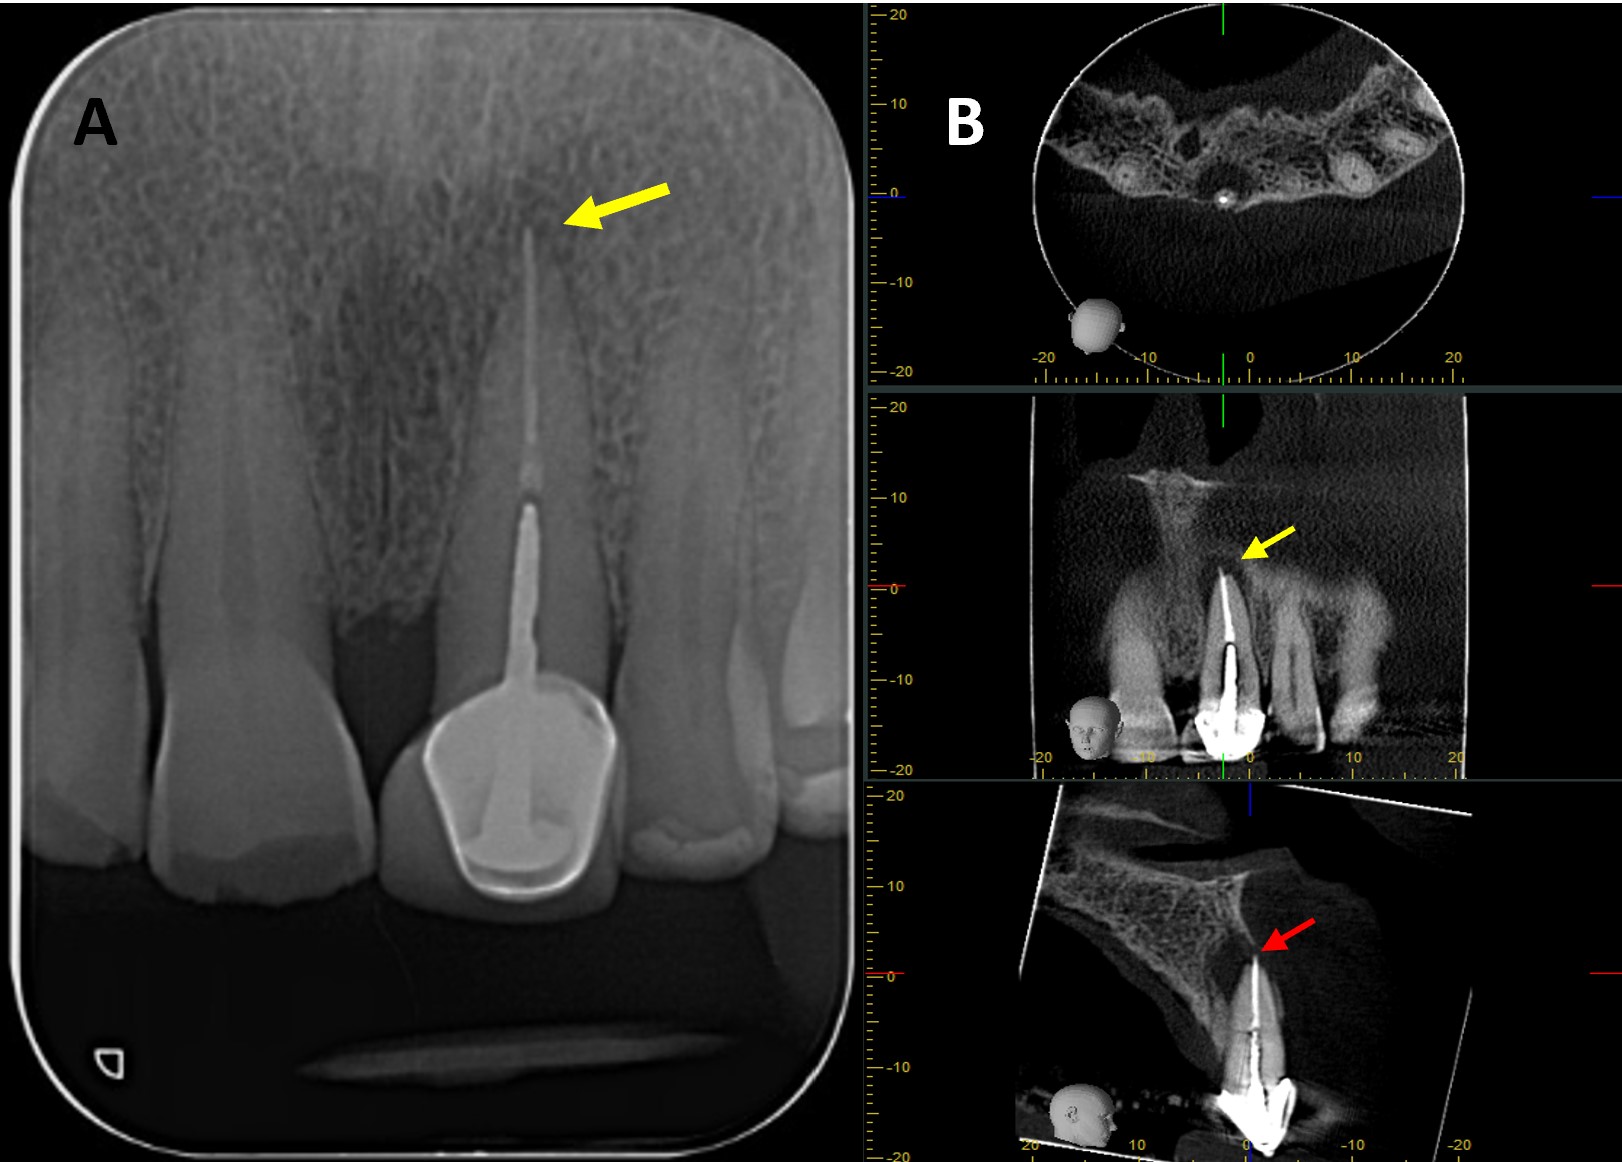

A 76-year-old male with no relevant medical history was referred to the postgraduate endodontics program (CES University Dental Clinic, Sabaneta, Colombia) for evaluation and management of tooth #21. Clinical examination showed a well-fitted metal-ceramic crown, normal probing, grade I mobility, tenderness to palpation and percussion, and fistula on the buccal mucosa. Cone beam computed tomography (CBCT) (J. Morita R100, Kyoto, Japan) at 90 mA, 8 kV, FOV 4 cm x 4 cm, and voxel size 0.5 mm showed a single canal with a post in the middle third of the root and extruded obturation material beyond the apex. The periapical lesion was visible on CBCT but not on periapical radiograph (Fig 1 A-B). The established diagnosis was a previously treated tooth with chronic apical abscess affecting tooth #21 (Fig 2-A). The proposed treatment plan was EMS, which was accepted by the patient after obtaining informed consent.

FIGURE 1. (A) Preoperative periapical radiograph of tooth #21, which the presence of a periapical radiolucency is not clearly. (B) Preoperative CBCT of tooth #21, presented in axial, coronal, and sagittal sections, reveals a hypodense area at the apical region consistent with a periapical lesion. The sagittal section demonstrates vestibular bone fenestration, as indicated by the red arrow. The yellow arrow denotes the presence of transapical obturation material in both the periapical radiograph and CBCT, as well as the existence of a post and prosthetic crown.